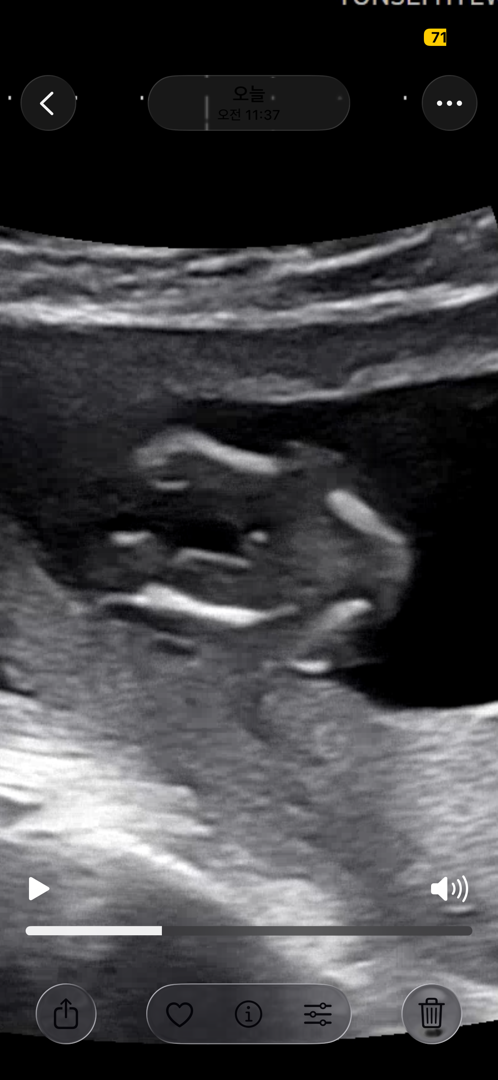

13주 초음파 보고왔는데 딸일까요 아들일까요???

다리사이에 저게 길쭉이는 안보이고 x알만 보이는걸까요 아님 살로 보이는거같기도하고 여자아이일까요?? 남자아이일까요 ?? 넘 궁금해용 ㅠ